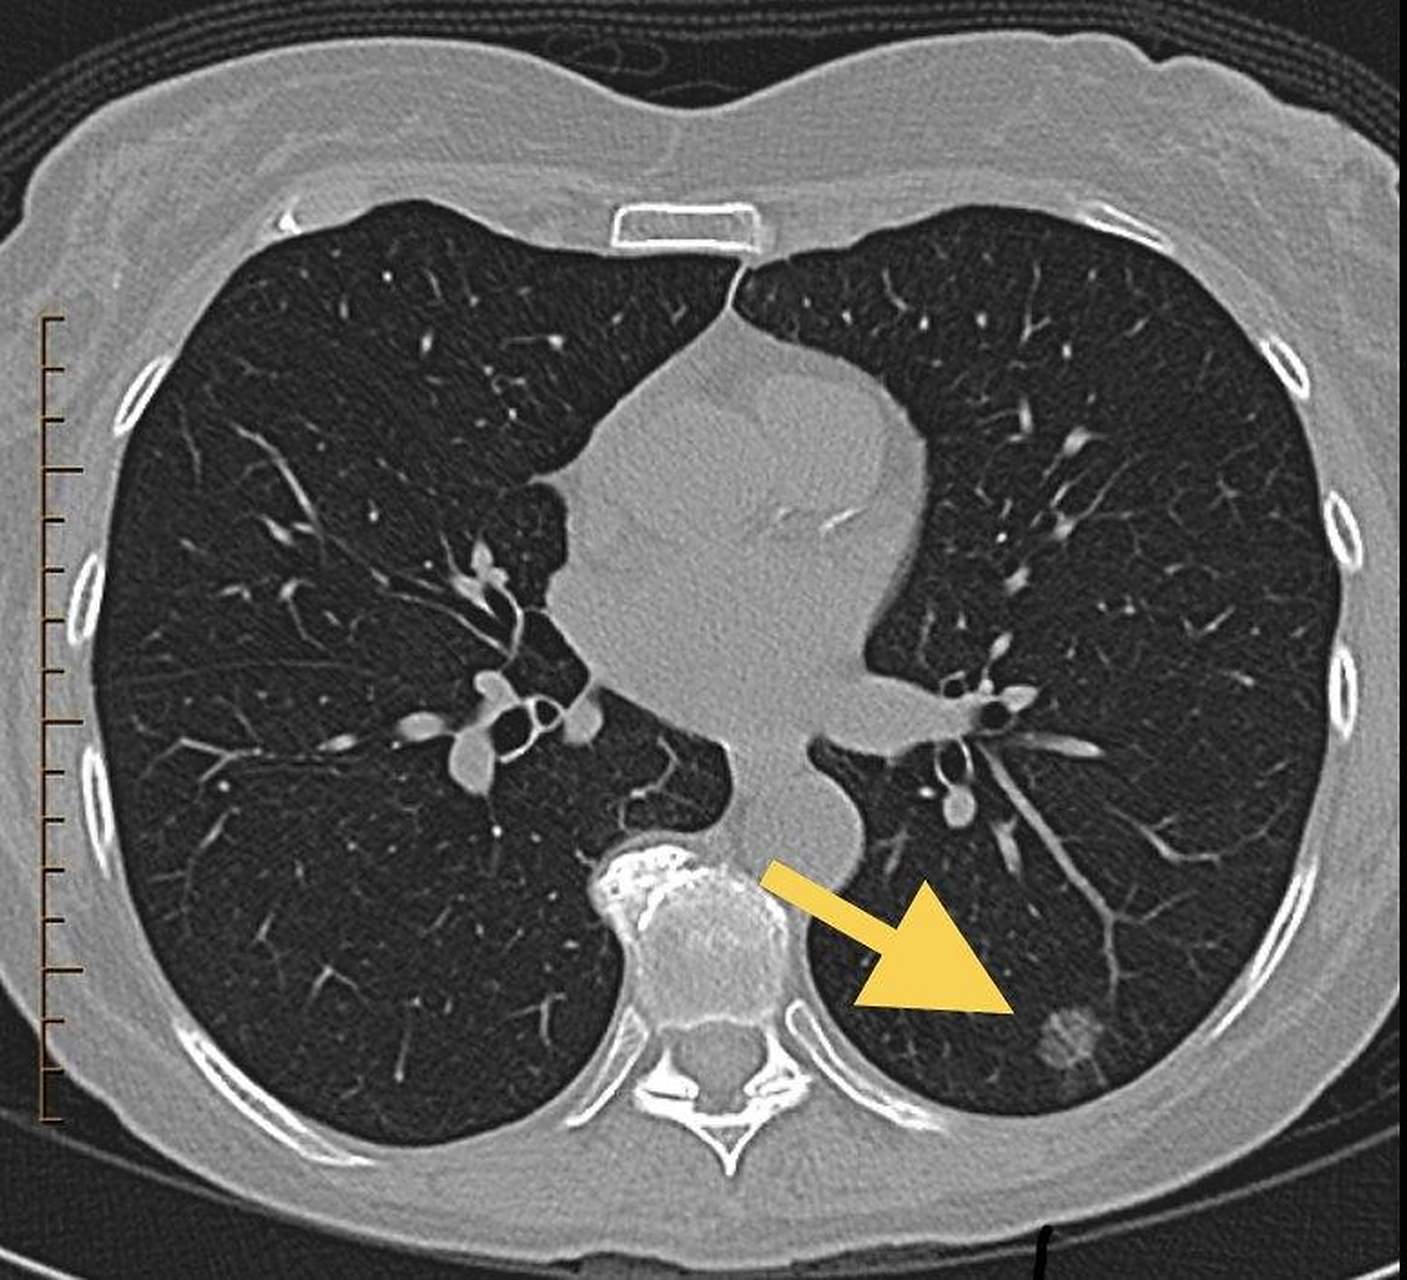

8mm混合磨玻璃肺结节当地建议做活检,我回复:手术不犹豫